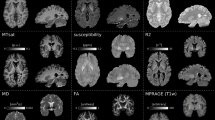

Fractional anisotropy (FA) values are plotted against step count and step length (SL) for the right (SL R) and left (SL L) leg under three conditions: A normal gait, B fast gait, and C dual-task. Dot-coloring: MDS UPDRS III FoG score ≥1: red, FoG score of 0: blue. Lower FA values, are associated with fewer and longer steps. Raw data points are presented along the model fit. PFDR - P-value corrected for False-Discovery-Rate (FDR), R² - the partial R² value for FA from the model - the amount of unexplained variance reduced by the FA value is appended as a percentage.

Fractional anisotropy (FA) values were plotted against gait velocity, cadence, and the percentage of stance time during the step cycle for each leg under three conditions: A normal gait, B fast gait, and C dual-task. Dot-coloring: MDS UPDRS III FoG score ≥1: red, FoG score of 0: blue. Lower FA values, indicative of greater microstructural complexity, are associated with faster gait velocity, higher cadence and shorter stance times. Raw data points are presented along the model fit. PFDR - P-value corrected for False-Discovery-Rate (FDR), R² - the partial R² value for FA from the model - the amount of unexplained variance reduced by the FA value is appended as a percentage.